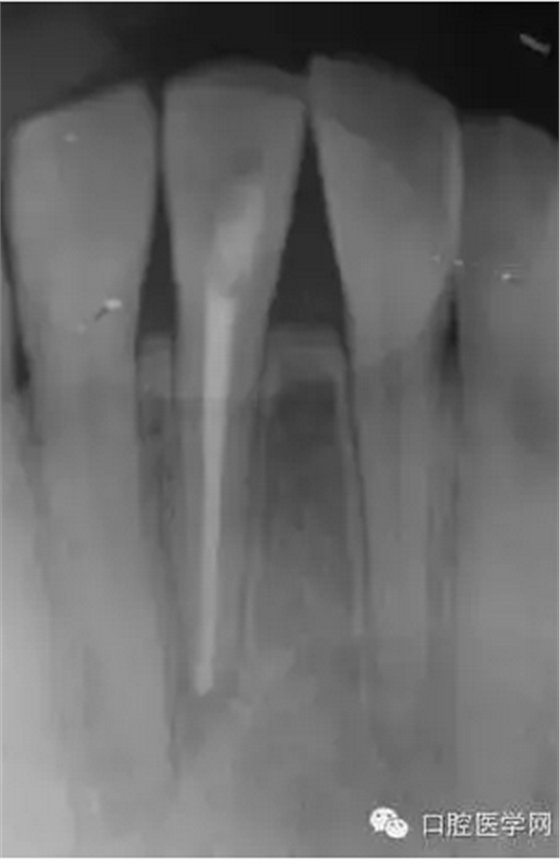

23歲女性患者,下頜右前牙的唇側(cè)有嚴(yán)重腫脹和疼痛。相應(yīng)部位有過外傷史,但記不起是什么時(shí)候了。放射線照片顯示以右下頜中切牙為中心,有波及右下側(cè)切牙及左下中切牙的大范圍的根尖周病變,臨床檢查時(shí),無齲壞,只發(fā)現(xiàn)右下中切牙略有變色,牙髓活力檢查(電子牙髓檢查及冷檢查)發(fā)現(xiàn),右下中切牙無反應(yīng),而鄰近齒表現(xiàn)為正常。判斷大范圍的根尖周病變的原因是受過外傷的右下中切牙的牙髓壞死,受周邊環(huán)境影響,發(fā)展為急性根尖周膿腫。

(圖 1) 初診的放射線照片